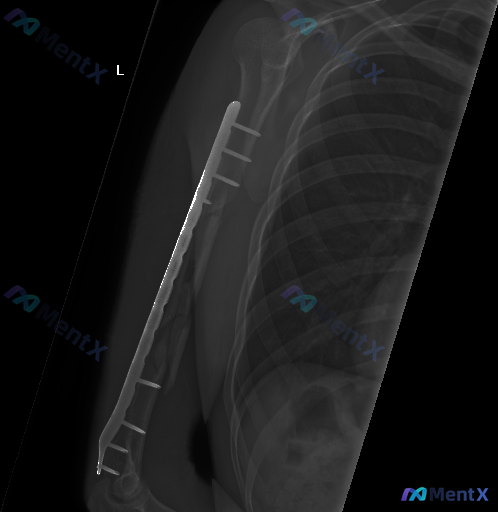

整理到一例左肱骨骨折内固定术后的复查影像资料,先把关键信息列出来,大家帮忙看看这种情况更往哪边考虑: 病例背景 左肱骨干骨折内固定术后复查(具体术后时间未明确说明)。 影像表现(左上臂+胸部X光) 1. 内固定情况:左肱骨外侧可见锁定加压接骨板及多枚螺钉固定,钢板、螺钉在位,未见明显松动、退出或断裂...